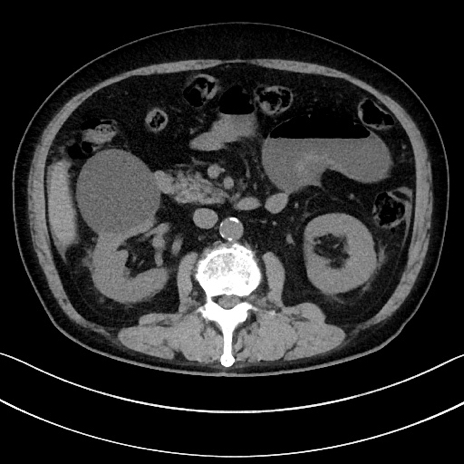

冠状断像

【症例】70歳代男性

【主訴】腹痛

【現病歴】今朝から腹痛あり。全体的に痛い。特に左上の方。排ガスが今日はない。冷や汗が出る。

【既往歴】直腸癌術後

【身体所見】左側腹部〜上腹部に圧痛あり。腹膜刺激症状明らかなではない。軽度反跳痛。左下腹部に術後瘢痕あり。

【データ】WBC 7700、CRP 0.02